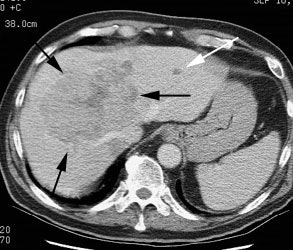

Hepatocellular carcinoma: The patient shown below had a large hepatocellular carcinoma (black arrows). Small satellite lesions were seen in other segments of the liver (white arrow). The FDG PET exam demonstrated only mildly increased uptake of tracer within the patients large primary lesion and the smaller satelite lesions could not be identified. |